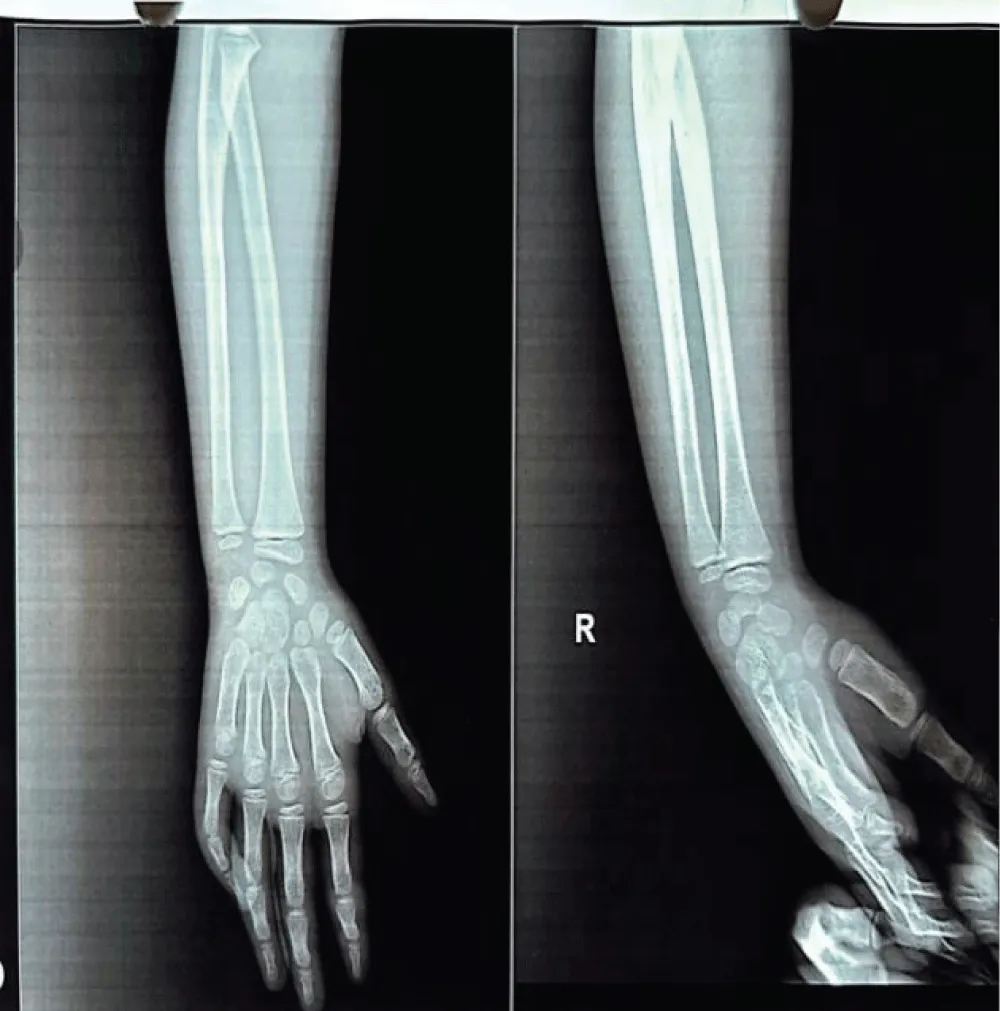

A mother with 6 year old female child presented to our Orthopedic Out Patient Department. She had not been able to move her right elbow in full range with restricted active and passive movements and appeared distressed. According to the informant (mother), she had been apparently well 2 months back when she was hit by rear wheels of a tractor while playing on the roadside. She developed pain and swelling in the elbow and was immediately rushed to the nearby hospital. Routine investigations, CT scan of abdomen and pelvis and X-ray of right elbow and hand were done. (Figures 1-3). All reports were normal except X-ray arm diagnosing undisplaced low lying supracondylar fracture of the right humerus (Figure 3). The child was admitted to the hospital and right upper limb was immobilized in an above-elbow plaster slab, with the elbow in 90o flexion (Figure 4). She was discharged after 4 days with reportedly normal radiographic findings.

Radiological imaging showed residual heterotopic ossification along the humerus, indicating incomplete resolution. Multiple radiographs of the right upper limb-including the arm, forearm, and elbow joint were taken during outpatient visits at the patient’s convenience and were compared over time to monitor progress (figure 7,8). A well-visualized radiograph obtained 10 months after the initial injury showed near-complete resolution of the heterotopic ossification (Figure 9).